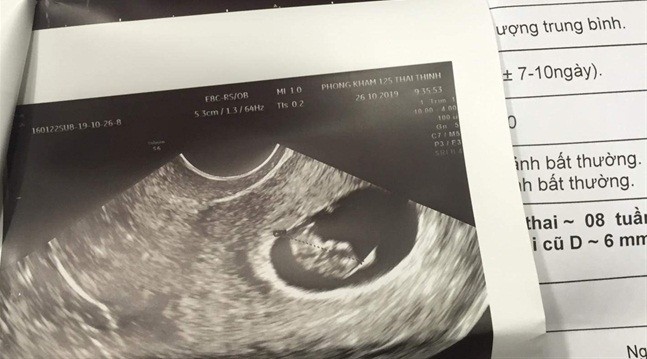

![]() |

| Kết quả siêu âm thể hiện chị A. đã mang thai 8 tuần tuổi |